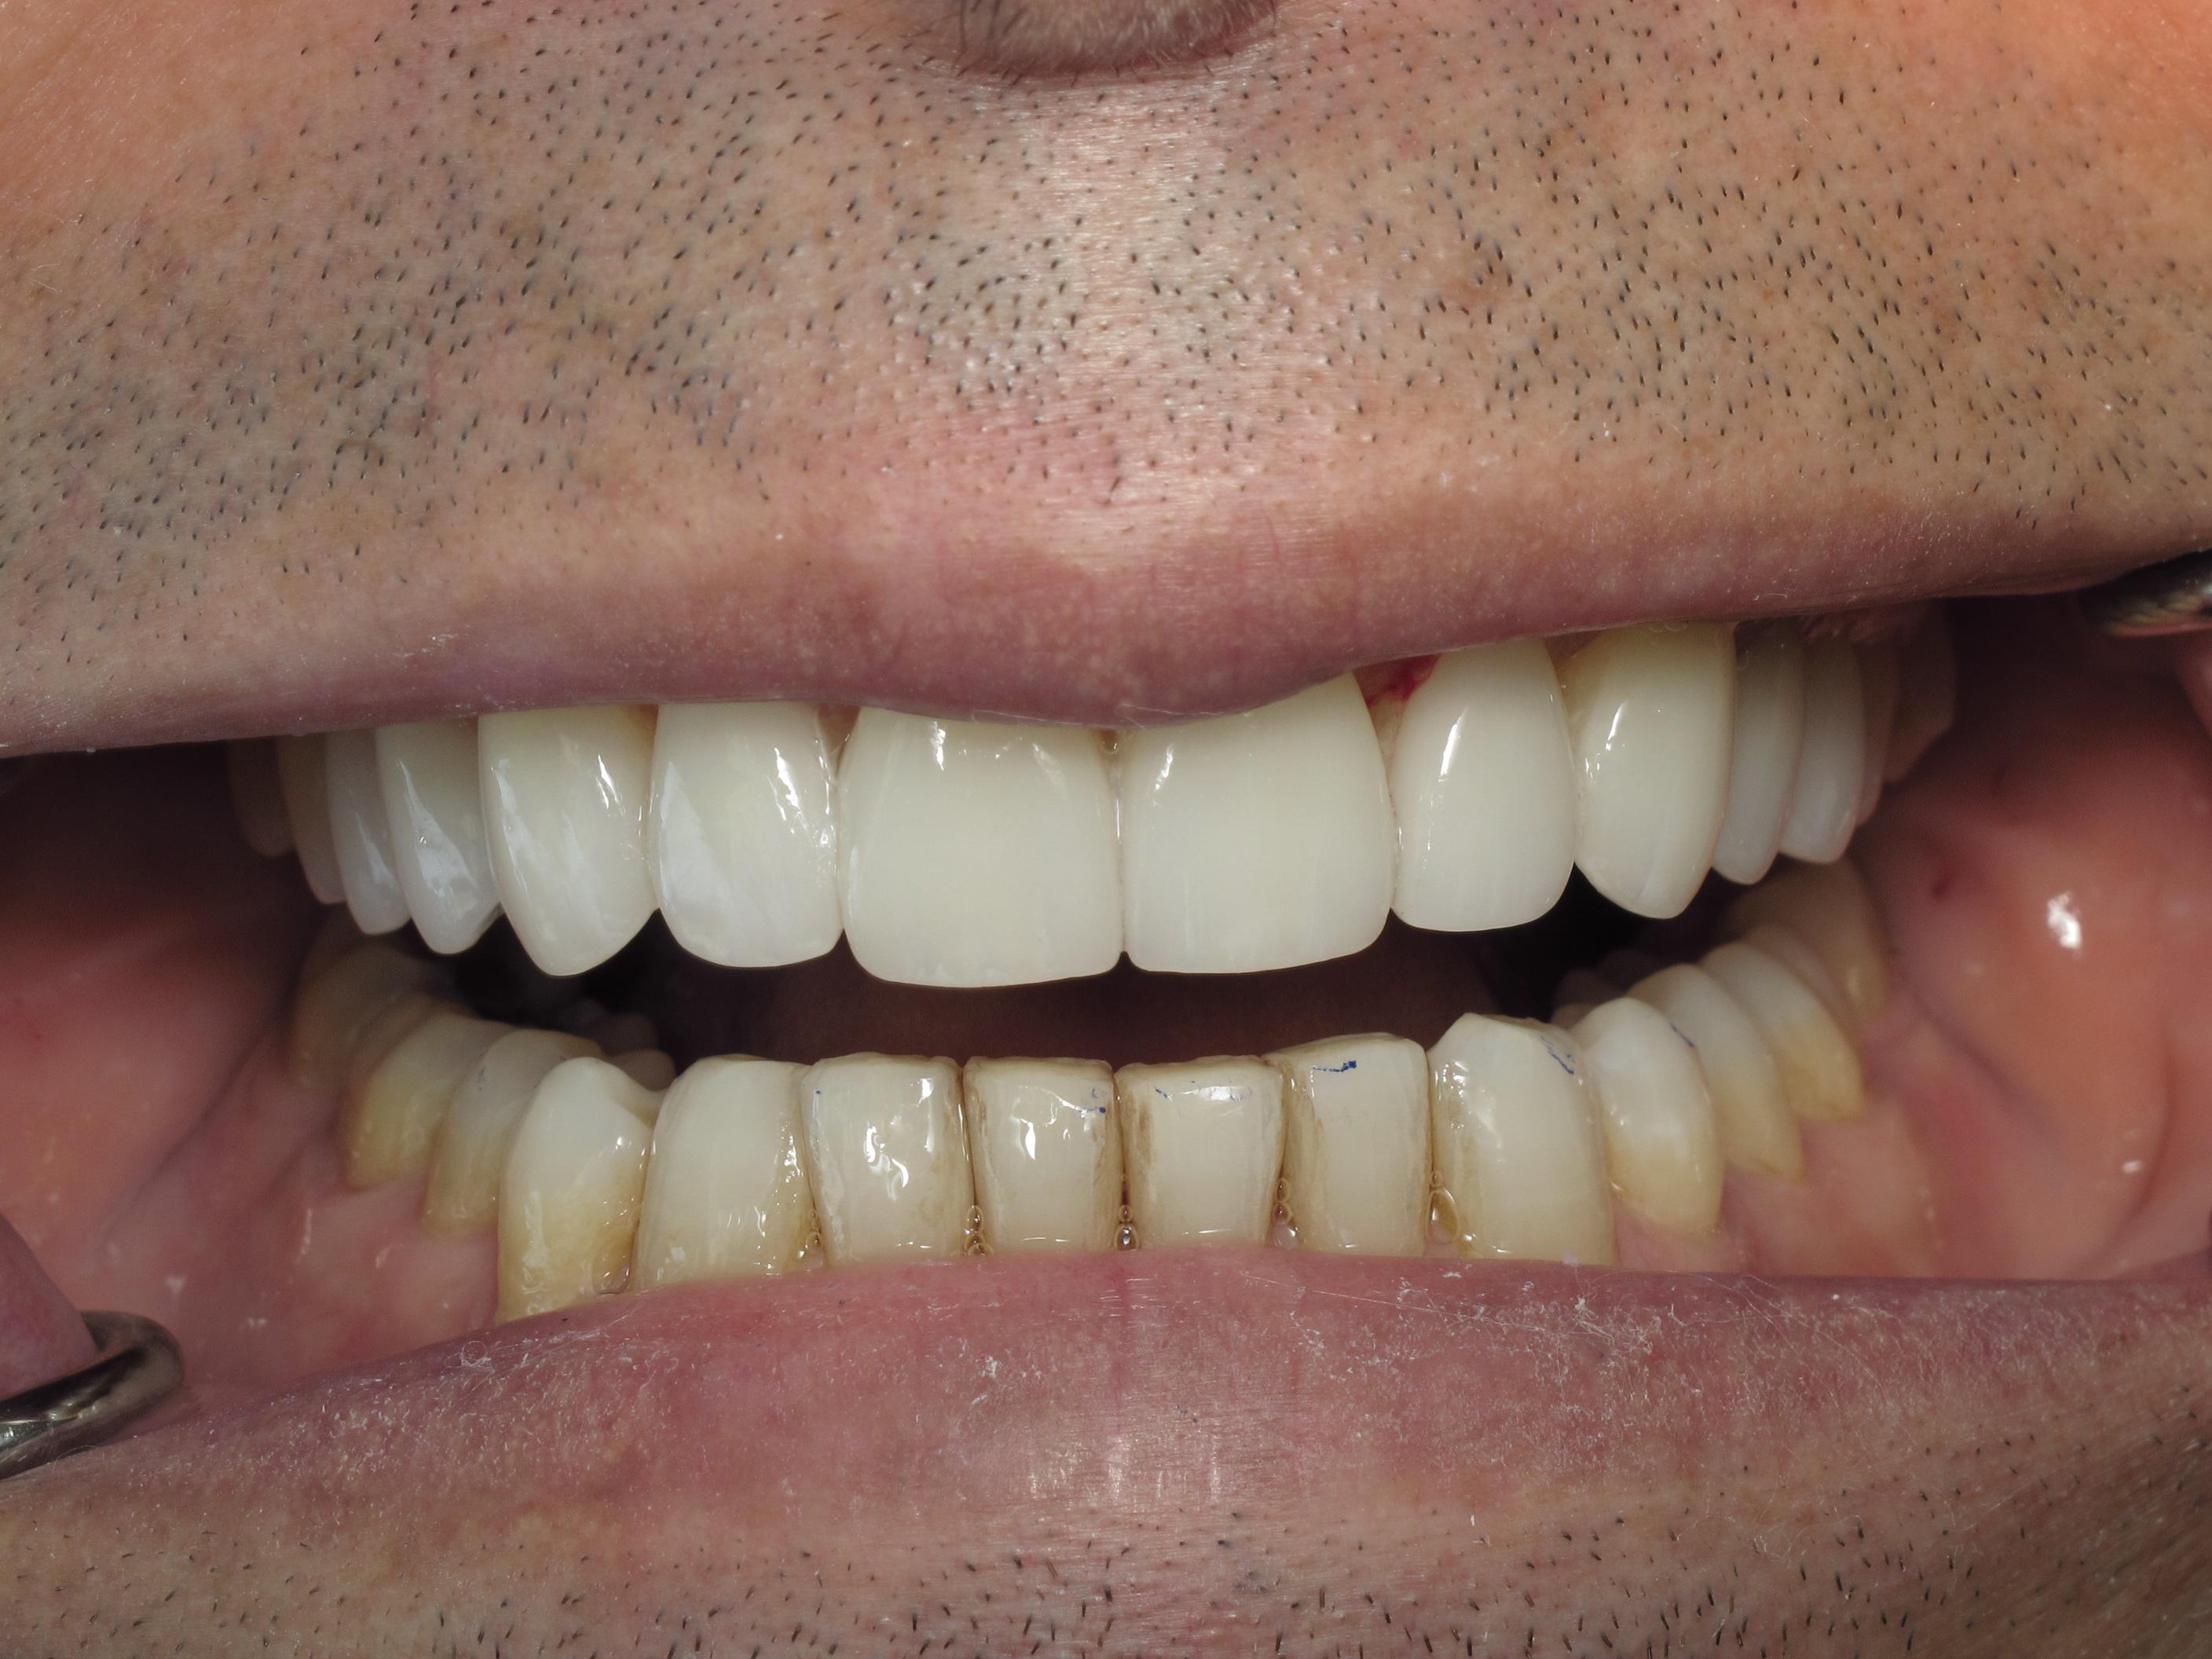

https://demo.discussdentistry.com/forums/topic/accident-victim-upper-arch-rehab/#post-26049 <![CDATA[Accident victim => Upper arch rehab]]> https://demo.discussdentistry.com/forums/topic/accident-victim-upper-arch-rehab/#post-26049 Tue, 30 Apr 2024 04:28:51 +0000 Amit Kumar The patient presents after falling in the bathroom and hitting his face on the countertop.  Previously, he had a PFM crown in the upper anterior.  He needed root canal therapy.

The patient is a stage performer (actor) and has appeared in some minor film roles, so he wanted to restore his teeth so that his smile would appear “white” on camera.

The patient’s lower teeth need attention and we will start the process once the patient’s finances have improved.

eMax material was used.  Pics were taken immediately after cementation.Before LeftBefore FrontBefore RightAfter FrontAfter LeftAfter Right